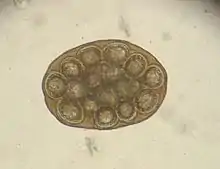

Hairworms are most commonly found as parasites in the gastrointestinal tract in cats, for example capillaria putorii. They are considered to cause little disease, but occasionally cause vomiting and diarrhea and, rarely, peptic ulcer disease with anemia.[6] The eggs of gastrointestinal hairworms are oval, about 60-70 × 35-40 µm in size, and can be detected by flotation techniques.[7]